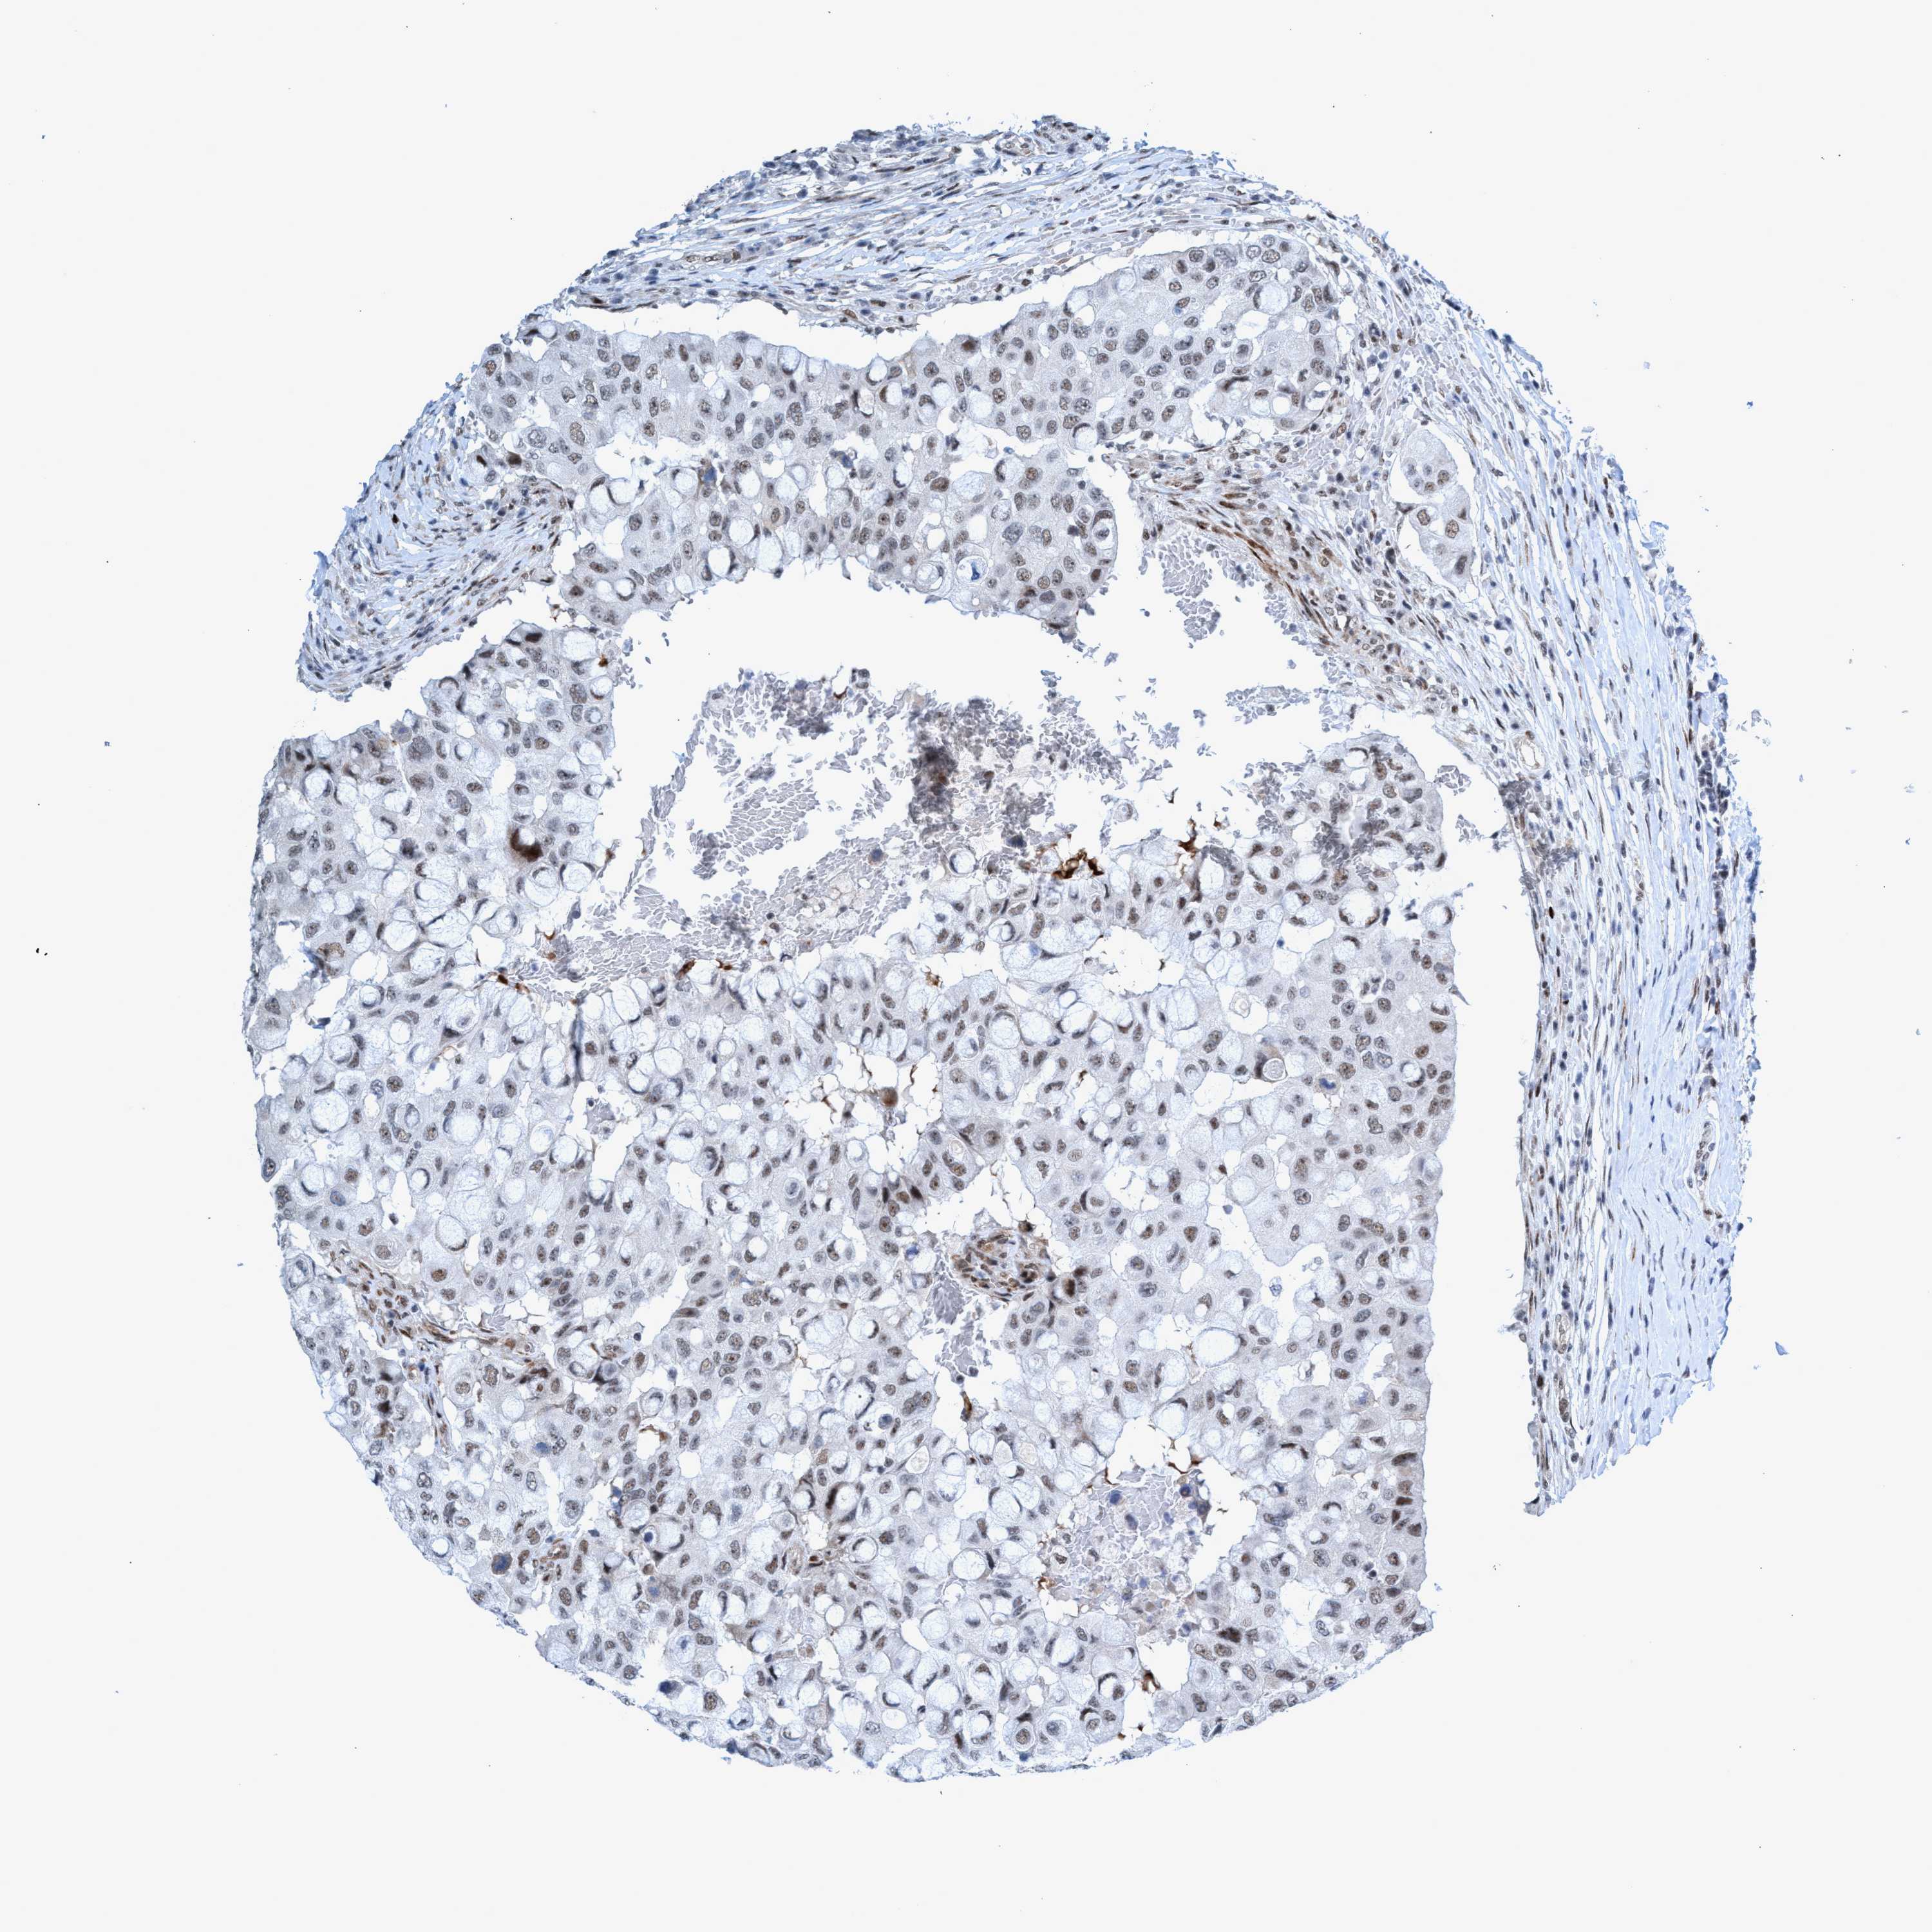

CANCER BREAST CANCER Show tissue menu

BRCA TCGA BRCA VALIDATION PROTEIN EXPRESSION